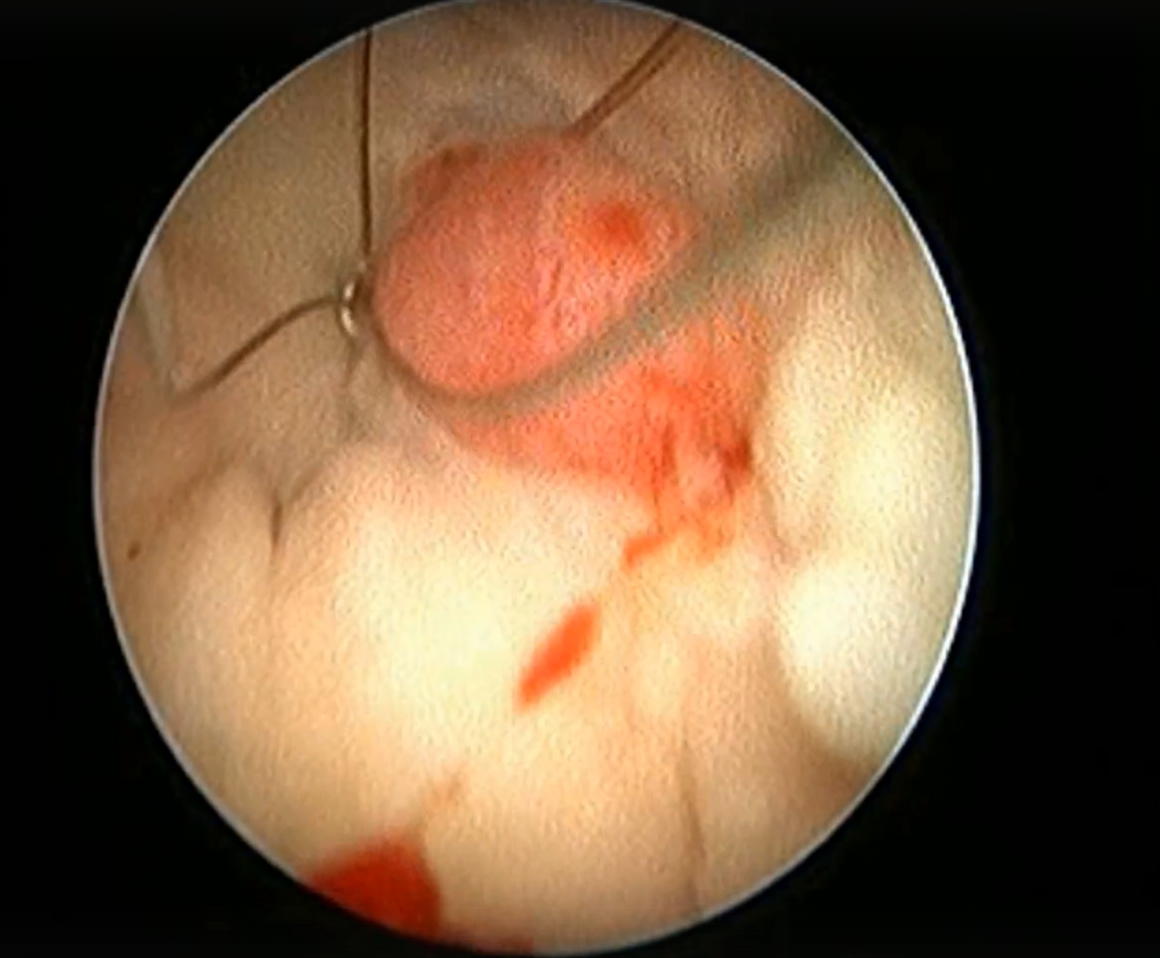

После вчерашней находки при проведении вагиноскопии у собаки Йоркширский терьера было проведено удаление новообразования в области влагалища с использованием монополярной коагуляции и диссекции с последующей абляцией тканей слизистой влагалища. Метод - вагиноскопия в водной оптической среде (стерильный раствор дистиллированной воды)

Это малоинвазивный способ хирургии, являющийся малотравматичным, обеспечивающим современный подход к патологиям репротракта. После данной манипуляции травматизм минимальный - происходит быстрое восстановление питомца без видимых клинических проявлений Видео с объектива эндоскопа можно посмотреть по ссылке https://vk.com/wall-232218233_17